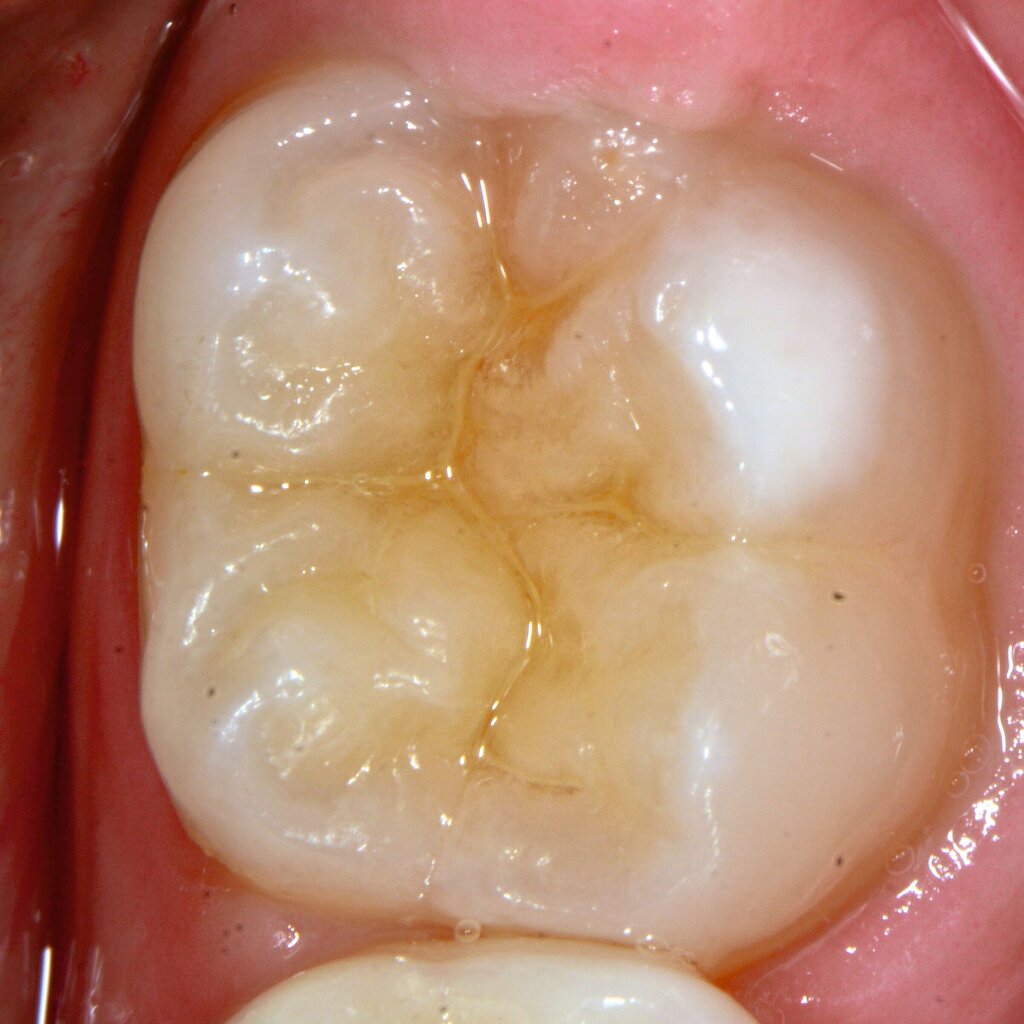

Das klinische Erscheinungsbild an bleibenden Zähnen zeigt typischerweise weißlich-gelbe bis gelblich-braune Opazitäten, die zumindest in einigen Bereichen durch eine scharfe Abgrenzung (engl.:„demarcated opacities“) zum gesunden Zahnschmelz charakterisiert sind (Abbildungen 3 und 4). Die abgegrenzten Hypomineralisationen befinden sich mehrheitlich im Bereich der inzisalen Kronenhälfte unabhängig von dem Auftreten an Front- oder Seitenzähnen. Die Ausprägung am Zahn kann dabei auf einzelne Areale oder Höcker begrenzt sein.

Für die Dokumentation und Klassifikation der MIH wurden verschiedene Systeme vorgeschlagen. Als historisch und veraltet gilt der (modifizierte) DDE-Index. Demgegenüber haben die Kriterien der EAPD – abgegrenzte Opazitäten (Abbildung 3 und 4), Schmelzeinbrüche (Abbildung 5), atypische Restaurationen (Abbildung 6) – mittlerweile die weiteste Verbreitung gefunden. Diese wurden 2003 erstmals zur Beschreibung der MIH auf empirischer Basis publiziert [Weerheijm et al., 2003] und den Jahren 2010 und 2022 im Rahmen der damaligen MIH-Workshops bestätigt [Lygidakis et al., 2010; 2022].